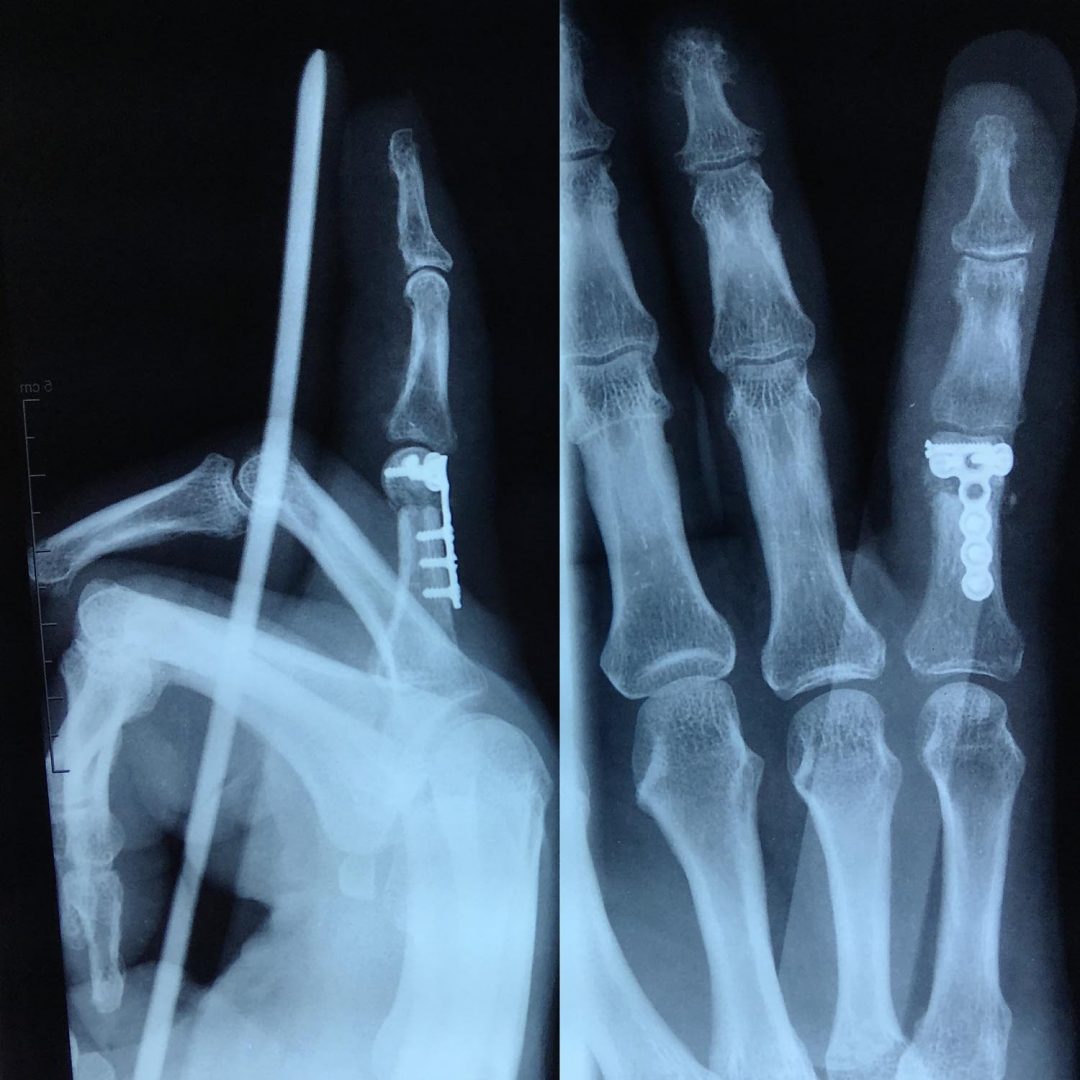

Phalange Cassée Petit Doigt. Un Jour En Chirurgie Orthopedique Et Traumatologique Fracture déplacée de la première phalange Chacun d'entre eux est constitué d'os qu'on appelle les phalanges Il peut être plus facile de repérer un désalignement ou une torsion sur les doigts extérieurs comme le petit doigt, l'index ou le pouce.

Doigt cassé Banque de photographies et d’images à haute résolution Alamy. Les fractures des phalanges, communément appelées fractures des doigts, sont des blessures courantes traitées. Les symptômes et le traitement d'une fracture de la phalange dépendent de la localisation et de l'intensité de la blessure.